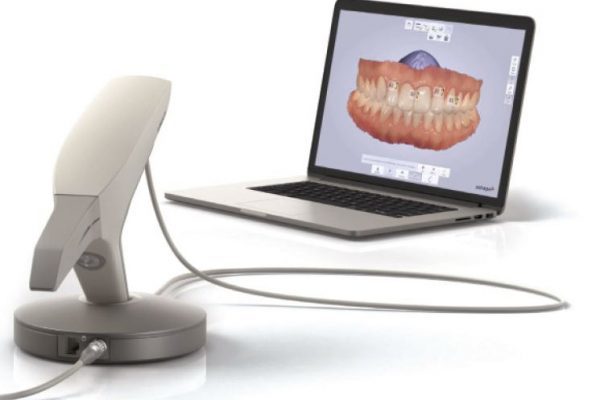

Benefit from digital impressions from £40

Intraoral scanners such as the 3Shape Trios, are handheld 3D scanning devices used to take digital impressions. CT Dent offers…

Private Practice